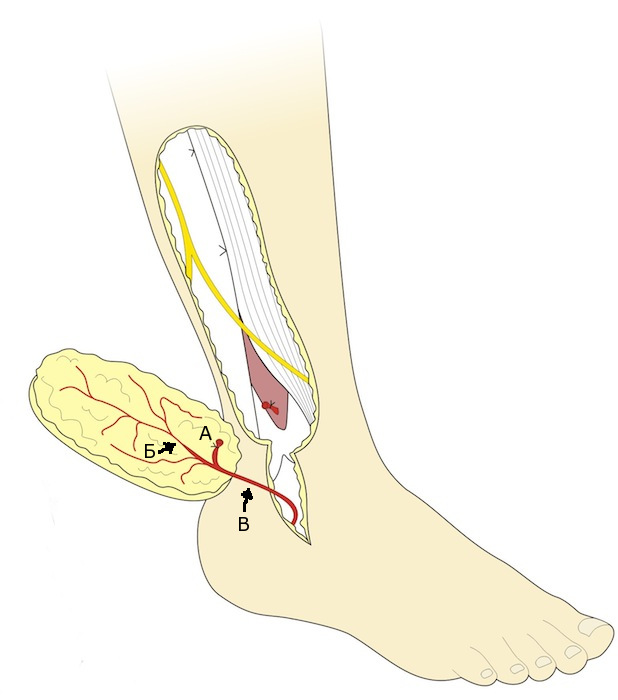

Сосудистая ножка формируется за счет дистального фрагмента малоберцовой артерии, которая проходит кпереди от лодыжки на стопу. В этом варианте формирования лоскута его кровоснабжение обеспечивается за счет ретроградного тока от дистальных анастомозов артерии. Ножка может быть выделена дистально до анастомозов с латеральной предплюсневой артерией на уровне пазухи предплюсны (рис. 6) [5].

Рис. 6. Островковый надлодыжечный лоскут на дистальном основании.

А- Лигированная перфорантная ветвь малоберцовой артерии, Б- Восходящая кожная ветвь в составе лоскута, В- Нисходящая ветвь

В некоторых случаях возможно продолжение дессекции до уровня бугристости пятой плюсневой кости. Перфорантная ветвь малоберцовой артерии легируется как можно глубже места отхождения кожной ветви к лоскуту. Для выполнения этого легирования может потребоваться создание небольшого раскрытия межкостной перегородки с целью лучшей визуализации малоберцовой артерии. Выделение сосудистой ножки до синуса предплюсны на 8 см. в длину дает возможность обеспечить большую дугу ротации для латерального надлодыжечного лоскута (Рис. 6Г). Дистальная ножка всегда сопровождается одной или двумя крупными венами, которые обеспечивают венозный отток.